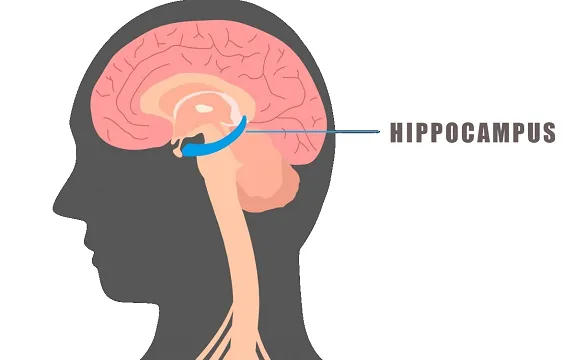

Research shows that in humans, spatial awareness is linked to a specific region buried deep in the brain called the hippocampus (figure 3). Scientists now know that this seahorse-shaped region of the brain (derived from the Greek words hippos, meaning “horse,” and kampos, meaning “sea monster”) functions as both a map and a memory system. The hippocampus is crucial to many parts of life. It allows us to orient ourselves in space and it gives us a sense of direction. You can think of the hippocampus as the brain’s spatial memory system.

The Brain’s Hippocampus (Fillit 2017)

In humans, the hippocampus performs an additional function by looking at experience, time, and place. This unique combination allows us to have what are called episodic memories. These are the memories that are linked to a particular place and time - such as where you were when you heard the news about September 11th. The hippocampus is responsible for retrieving these events from the past. It is thought that this capability advanced in humans during the hunter-gathering days as an extension to the spatial functions found in other animals6.

Much of what we know about the hippocampus and its role in memories can be attributed to a man with no memory at all. As a young boy, Henry Molaison (commonly known as Patient HM) was hit by a car while riding his bike and suffered a brain injury. Soon after that, he began to experience severe epileptic seizures. In 1953, at the age of 27, he decided to undergo experimental brain surgery and have his hippocampus removed. His seizures immediately disappeared, but so did his recent memories.

With Patient HM, it became clear that the hippocampus plays a vital role in memory and storage of memories. It was determined that incoming experiences sit in the hippocampus for a period of time as they are being evaluated for storage. If the experience is strong enough or if we think about the event from time to time, the hippocampus moves this memory to the cortex for long-term storage. The hippocampus coordinates this recording and storing of memories.

This explains why Patient HM could not create new memories. Additionally, because the hippocampus also plays a role in memory retrieval, he was not able to get access to the long-term memories that were stored in the cortex prior to the surgery. His brain could process immediate, sensory experiences but it had no mechanism to store them7.

The London cab driver studies have shown that the hippocampus plays a vital role in spatial navigation. While creating these mental brain maps, it is thought that the hippocampus grows new neurons and that these neurons further make connections with one another. Researchers think that these findings could have important implications for people with brain damage for diseases such as Alzheimer’s and Parkinson’s10.

We know that the hippocampus is important for spatial thinking, navigation, and memory creation - and we’ve seen with Patient HM what happens when it’s completely removed. But, what do we know about the hippocampus when it’s not functioning properly?

Often, the first signs of Alzheimer’s in an individual is a sense of disorientation and getting lost in familiar environments. Additionally, individuals begin to lose episodic memories11.

We now know that Alzheimer’s disease results in a progressive loss of tissue throughout the brain, particularly in the hippocampus. The most rapid loss of tissue occurs in the hippocampus in the earliest stage of the disease. This progressive shrinking is responsible for the disorientation and loss of memory that is the hallmark symptom of Alzheimer’s12. These early signs are tied to a loss of function in the hippocampus.

Currently, there is no effective treatment for Alzheimer’s, however, there is increasing interest in identifying the disease at its earliest stages. The London cab driver studies showed that the brain has the ability to grow new neurons in the hippocampus and that those neurons make new connections. This might explain why the current thinking with Alzheimer’s is that early detection and intervention may be the most effective way to combat the disease12.

Neuroscientist Véronique Bohbot thinks that intervention, focused on executing the hippocampus might help offset age-related impairments or even neurodegenerative disease. She says, “If we are paying attention to our environment, we are stimulating our hippocampus, and a bigger hippocampus seems to be protective against Alzheimer’s disease”.